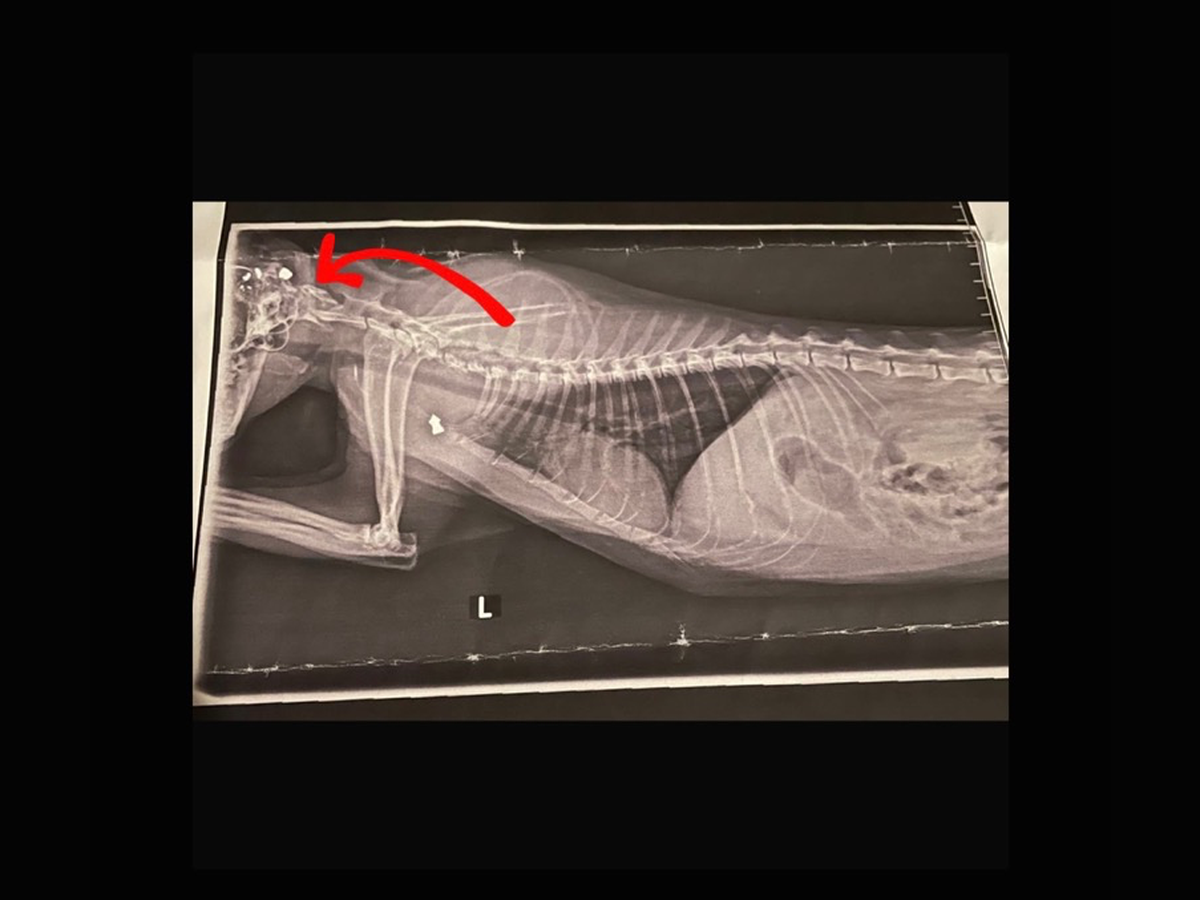

Ein paar Halbstarke, nicht Ortsansässige schossen mit Luftschussgewähren mehrfach, aus nächster Nähe auf die wehrlose Lilly und verletzten sie tödlich.

Ein Schuss ging ins Genick und zersplitterte und ein Schuss ging in die Lunge.